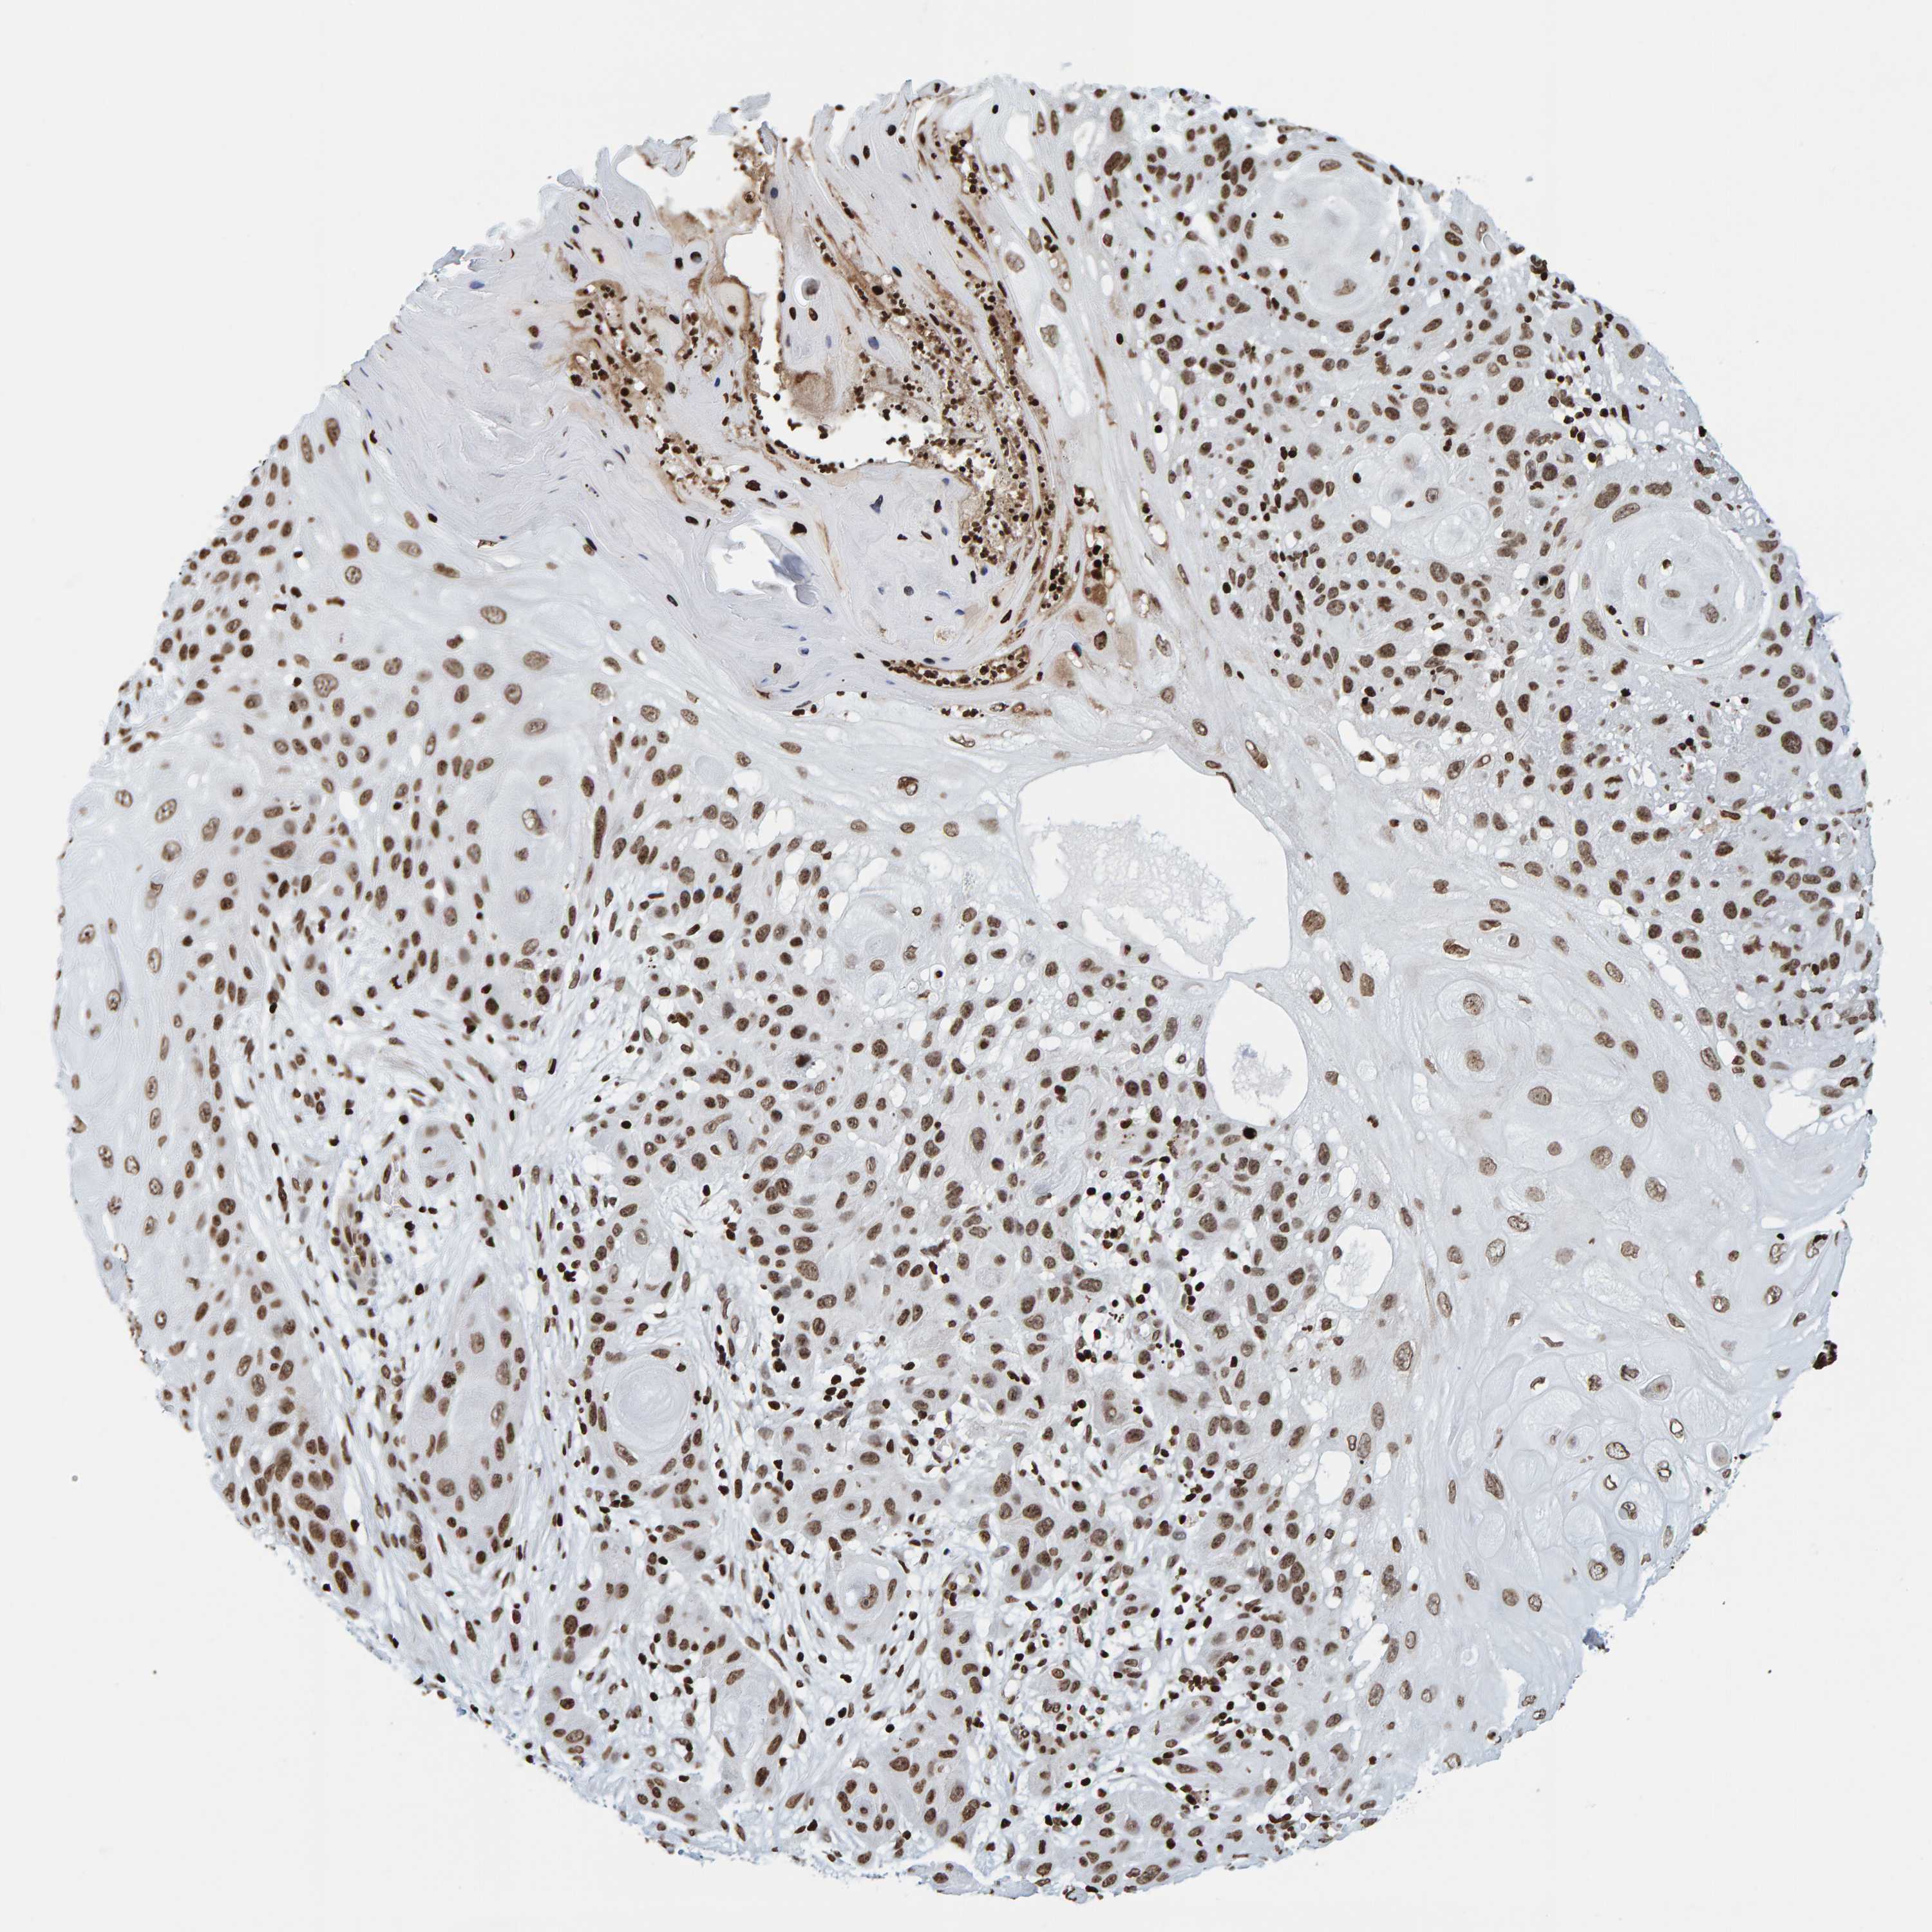

CANCER SKIN CANCER Show tissue menu

SKIN CANCER - Protein expressioni

A mouse-over function shows sample information and annotation data. Click on an image to view it in a full screen mode. Samples can be filtered based on level of antibody staining by selecting one or several of the following categories: high, medium, low and not detected. The assay and annotation is described here.

Each image is clickable and will lead to virtual microscopy that enables deeper exploration of all samples and also displays staining intensity scores, fraction scores and subcellular localization as well as patient and tissue information for each sample.

Antibody HPA023378

Basal cell carcinoma

Squamous cell carcinoma, NOS

Squamous cell carcinoma, metastatic, NOS

Squamous cell carcinoma in situ, NOS

Adnexal tumor, benign